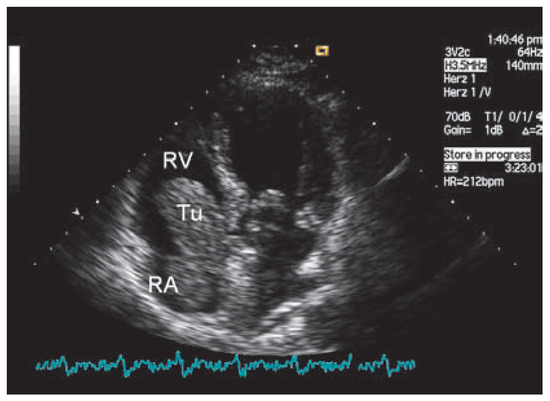

Endometrial Stromal Sarcoma—A Rare Tumor Invading the Heart

by Jens Seiler, Volkhard Göber and B. Nazan Walpoth

A 47-year-old female patient presented with progressive dyspnea on exertion, abdominal pain, loss of weight and tachycardia [...] Full article